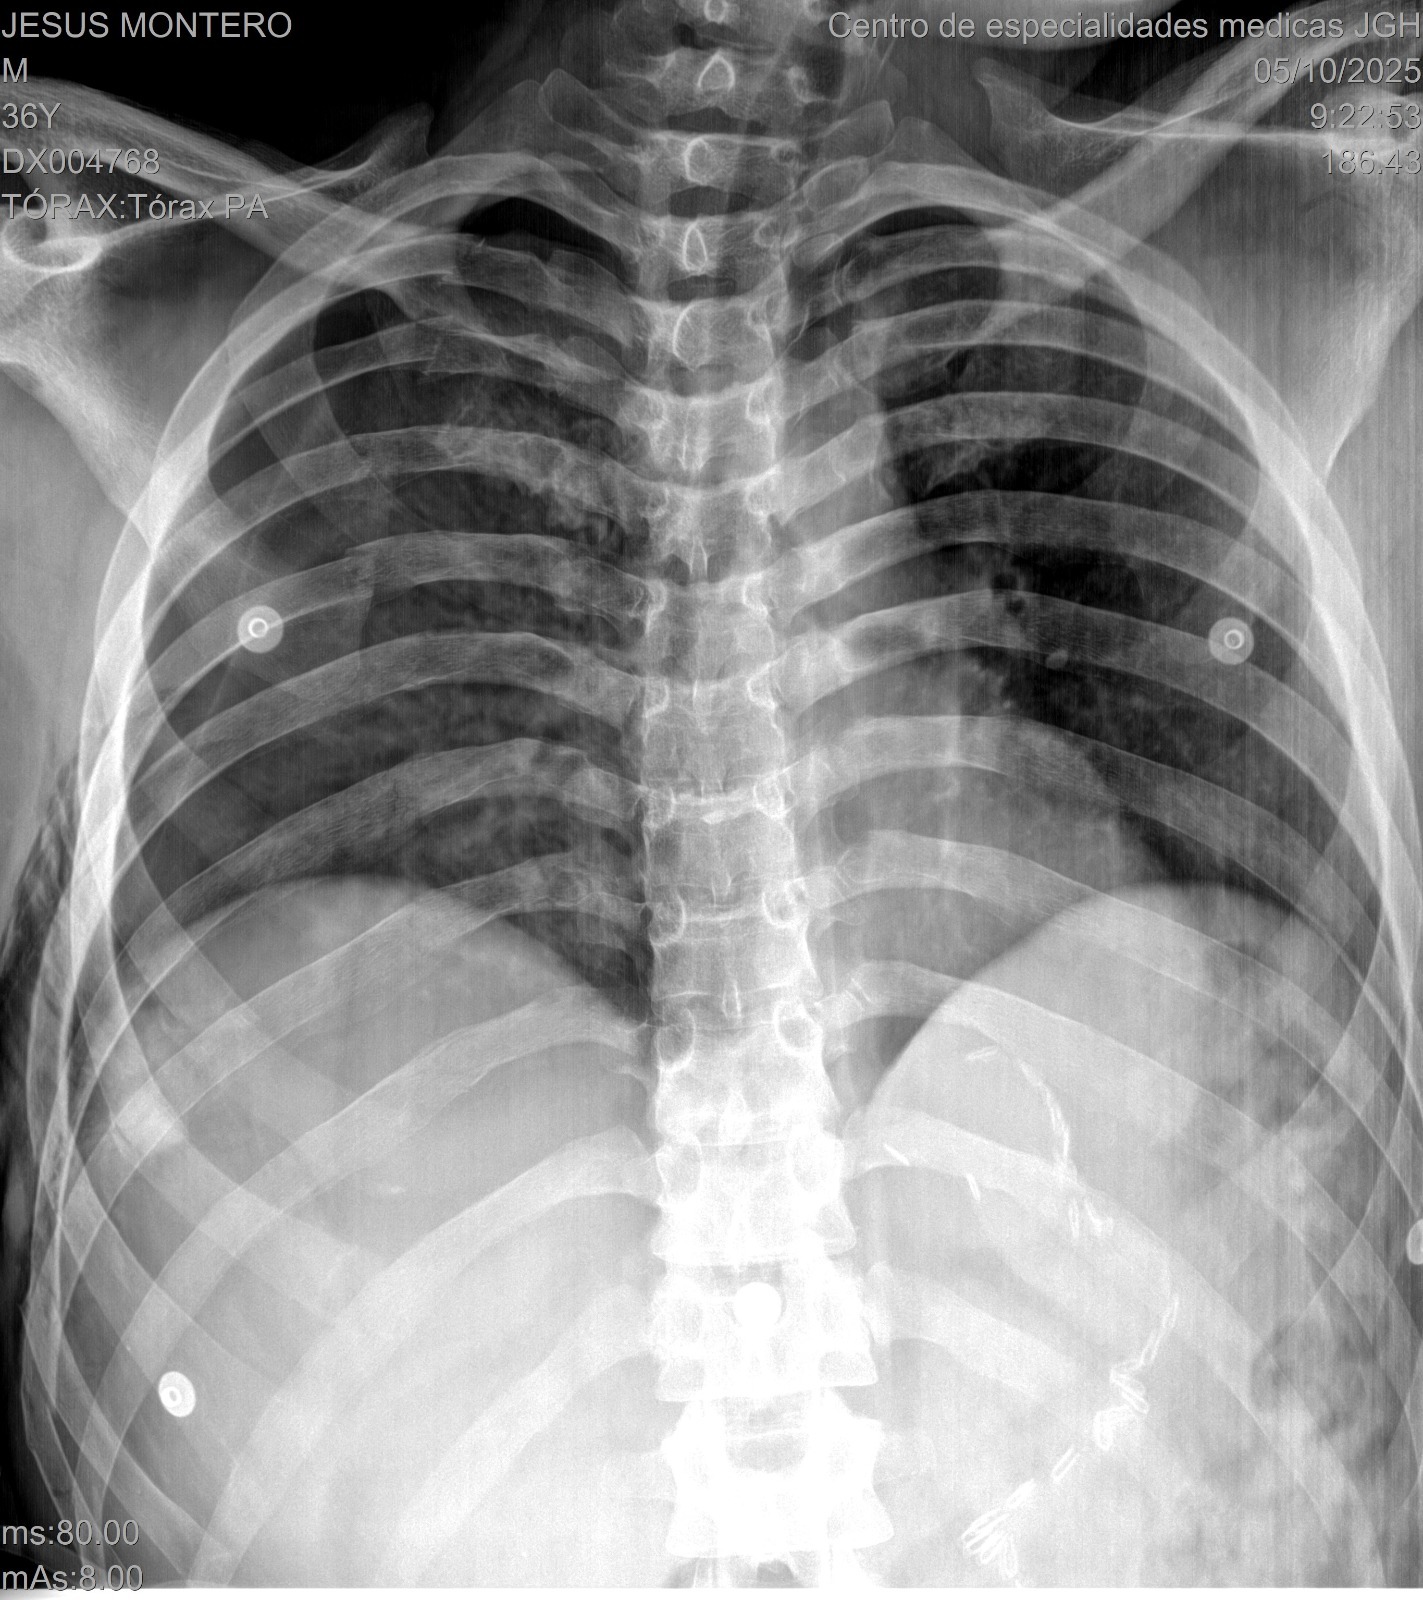

El pasado sábado por la noche, nuestro querido Jesús Montero, ex jugador de Grandes Ligas, sufrió un grave accidente de motocicleta. Actualmente se encuentra en estado delicado, con múltiples fracturas en la pierna, varias costillas rotas, pulmones y organos bastantes comprometidos. Los médicos han debido mantenerlo en un coma inducido para facilitar su oxigenación y estabilizar su condición. Tambien se le estara realizando Dialisis para ayudar al sistema renal.

Jesús continúa en la UCI, bajo pronóstico reservado. Aún sigue en diálisis, ya que sus riñones no han respondido como esperamos. Fue sometido a una cirugía para estabilizar su pierna, y aunque el procedimiento fue exitoso, todavía necesitamos avanzar con una cirugía en la zona del tórax, necesaria para su recuperación.

Last Saturday night, our dear Jesús Montero, former Major League Baseball player, was involved in a serious motorcycle accident. He is currently in critical condition, with multiple fractures in his leg, several broken ribs, and severe lung and organ injuries.

Doctors have kept him in an induced coma to help with oxygenation and stabilization, and he is also undergoing dialysis to support his kidneys.

Jesús remains in the ICU, under critical condition. He continues on dialysis, as his kidneys have not yet responded. He recently underwent surgery to stabilize his leg, which was successful, but he still needs to undergo a chest surgery, which is complex but necessary for his recovery.